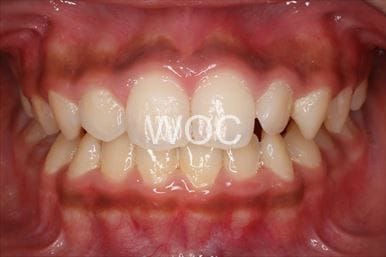

治療前2

治療後2